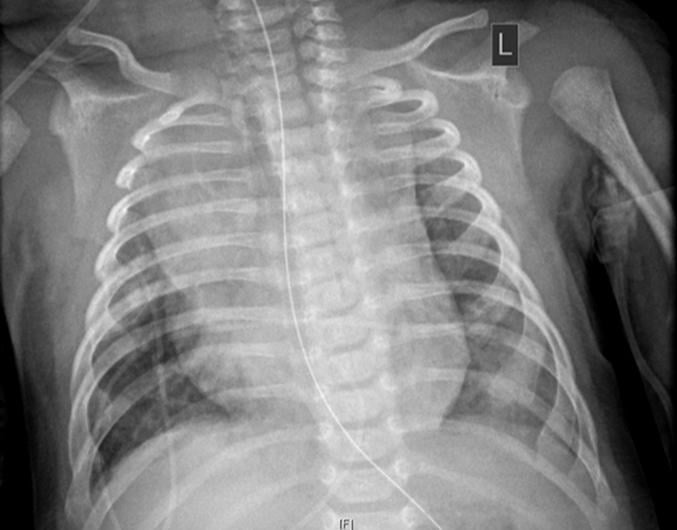

This photo gallery shows the variety of radiological presentations of COVID-19 (SARS-CoV-2) in medical imaging, including computed tomography (CT), radiograph X-rays, ultrasound, echocardiograms and magnetic resonance imaging (MRI). The radiology images show examples of typical COVID pneumonia in the lungs and the numerous complications the virus causes in the body in multiple organs, including the brain, kidneys, heart, abdomen and vascular system.

Ultrasound, especially hand-held ultrasound imaging devices, have become a primary imaging modality for novel coronavirus because of the ease to bag the device and sterilize it after use. CT and mobile X-ray systems are also used as front-line imaging systems for COVID-positive or suspected COVID patients.